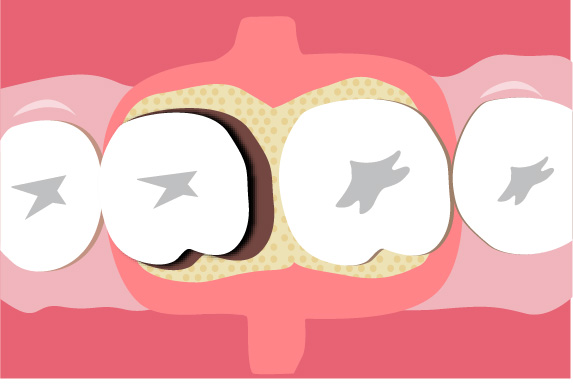

歯周組織再生療法は施術の難易度が高く、ほとんどの歯科では扱っていない内容です。